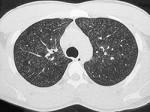

女,25岁,养鸽,咳嗽,咳痰,结合CT图像,最可能的诊断是 ( )A.肺泡癌B.肺结核C.肺隐球菌病D.支气管肺炎E.肺曲菌病